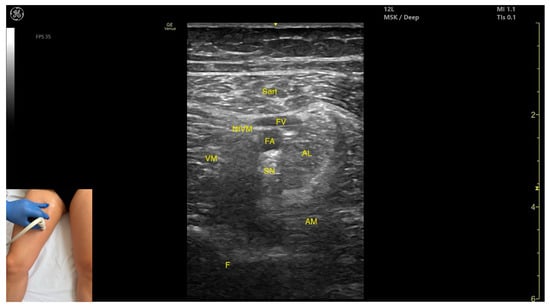

3.5. Sartorius (Sart)

3.5.1. Overview

3.5.2. Ultrasound Identification

3.5.3. Key Ultrasound Landmarks

- Muscle position: It is the most superficial muscle in the anterior compartment of the thigh. Deep and lateral to the sartorius lies the vastus medialis; deep and medial to the sartorius lies the adductor longus. At this level, the adductor canal is visualized beneath the Sart, containing the femoral artery, femoral vein, saphenous nerve, and nerve to vastus medialis.

- External fascia: A pronounced fascia separates the Sart from the subcutaneous plane, vastus medialis, adductor longus, and adductor magnus, aiding in precise botulinum toxin injection.

- Dynamic evaluation: During dynamic evaluation, scanning proximally toward the hip joint, at the proximal third of the anterior thigh, the adductor longus thickens medial and deep to the Sart, while the rectus femoris appears deep and lateral. At this level, the adductor canal shifts to lie medial to the Sart and lateral to the adductor longus. During distal scanning toward the knee joint, in the distal third of the anterior thigh, the gracilis is seen medial to the Sart, and the vastus medialis lies deep and lateral to it. Muscle contraction is visible during hip flexion, abduction, and internal rotation, as well as knee flexion maneuvers.

3.5.4. Clinical Implications and Injection Strategy

3.7. Adductor Longus (AL)

3.7.1. Overview

3.7.2. Ultrasound Identification

3.7.3. Key Ultrasound Landmarks

- Muscle position: It is the most superficial muscle mass at this level. Lateral to it lies the sartorius muscle, and medially, the gracilis muscle. The adductor canal is also visualized laterally.

- External fascia: It presents a pronounced fascia that separates it from the adductor magnus, adductor brevis, sartorius, and gracilis muscles during botulinum toxin injection.

- Dynamic evaluation: During dynamic evaluation, scanning proximally toward the hip joint, the adductor brevis, which lies deep to the adductor longus, becomes more prominent. Scanning distally toward the distal third of the medial thigh, the adductor longus gradually decreases in thickness until it disappears from view, at which point the gracilis and sartorius muscles become adjacent (Video S2). Contraction is visible during hip adduction and internal rotation maneuvers.

3.7.4. Clinical Implications and Injection Strategy